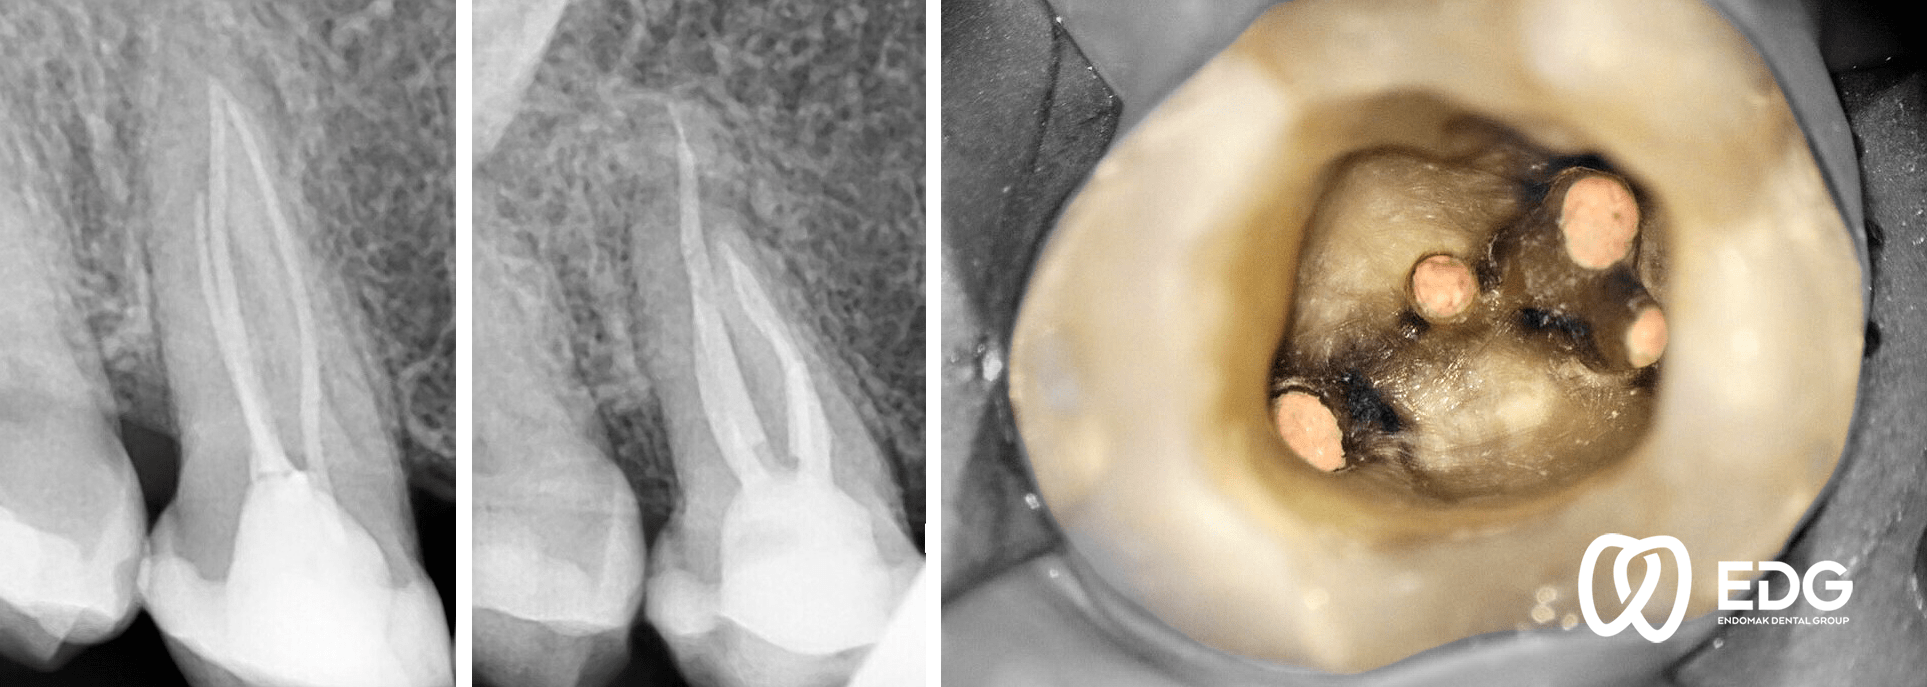

Microscopic Endodontic Treatment (MET) – retreatment of previously treated toothMade by Dr. Gjorge GudevEnjoy it !

Με το μικροσκόπιο, ένα υπερσύγχρονο εργαλείο για ενδοδοντική θεραπεία με πανίσχυρη μεγέθυνση, η απεικόνιση της εσωτερικής κατασκευής της οδοντικής κοιλότητας και των ριζικών καναλιών είναι πάρα πολύ βελτιωμένη. Η απεικόνιση αυτή είναι πολύ σημαντική για την ενδοδοντική θεραπεία επειδή η ακριβής ανίχνευση των ριζικών καναλιών η επιτυχής θεραπεία τους οδηγούν στη μακροχρόνια πρόβλεψη για τη διατήρηση του δοντιού.

Microscopic Endodontic Treatment (MET) step by step procedure. Enjoy it!Made by Dr. Gjorge Gudev